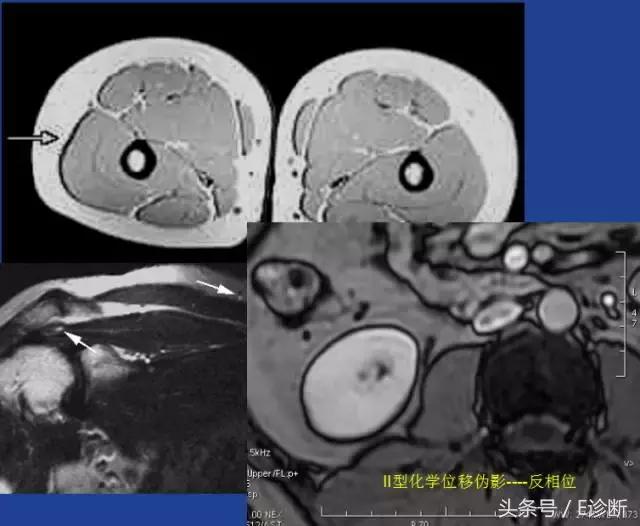

化学位移伪影

不同分子中氢质子以稍有不同的频率进动。在梯度场内,这些氢质子的位置将会被错误记录。

水内的质子相对向更高频率编码方向运动,而脂肪则相反。

位移导致在较低频率发生重叠,而较高频率处信号衰减。

水的进动稍快于脂肪中的质子进动。差异:3.5ppm

出现在频率编码方向上(常规FSE序列或梯度回波)。在较低频率的方向出现一条亮带,而较高频率的方向出现一条暗带。

由于水和脂肪的振动频率不同,在一小段时间后,将出现水在脂肪前360°的相位。这时两者的自旋将处在完全相同的相位中。同样,在某一个时间点也可能出现两者180°相位差的情况。这种同相位和反相位的情况被称为II型化学位移伪影。

以1.5T为例,当TE=2.3时,正好处在水脂反相位的情况,当脂肪包绕的脏器周围将出现一条暗的边界(水信号和脂肪信号相减),称为钩边效应。

II型化学位移伪影在临床诊断中意义重大,对于细胞内含脂性病变(脂肪肝、肾上腺腺瘤)等的诊断非常重要。